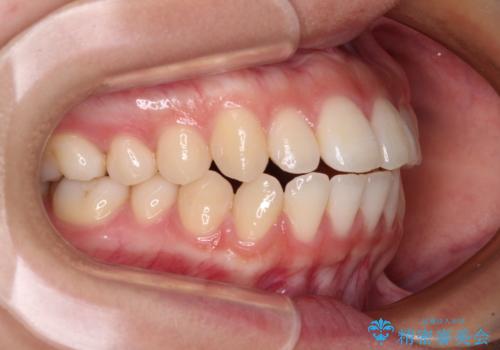

- 口元の突出感と上下前歯のズレを気にして来院された患者様です。

舌の突出癖により上下の前歯は非接触となっている状態でした。

突出感改善のため、上下左右の第一小臼歯4本を抜歯し、ワイヤー装置にて矯正治療を行うこととしました。

舌のトレーニングをしっかりと行ってくださり、予定通りの期間で理想的な仕上がりを達成することができました。